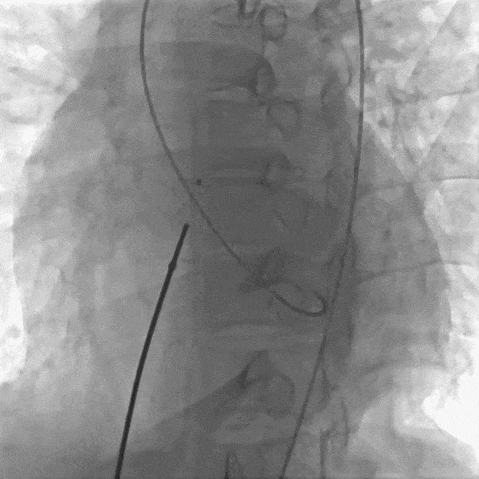

患者局麻后穿刺右股动脉及股静脉,经股动脉送入猪尾导管分别行左心室造影+主动脉根部行根部造影提示主动脉窦瘤破裂(无冠窦-右心房),持续大量左向右分流。明确病变位置后建立股动静脉轨道,经右侧股静脉送入输送鞘并送入先健12/14mm PDA封堵器。再次造影无分流,超声提示窦瘤破裂封堵完好,基本无残余分流,主动脉瓣未受影响。

建立轨道后再次造影证实

植入PDA 12/14封堵器后先行冠脉造影评价有无影响冠脉血流